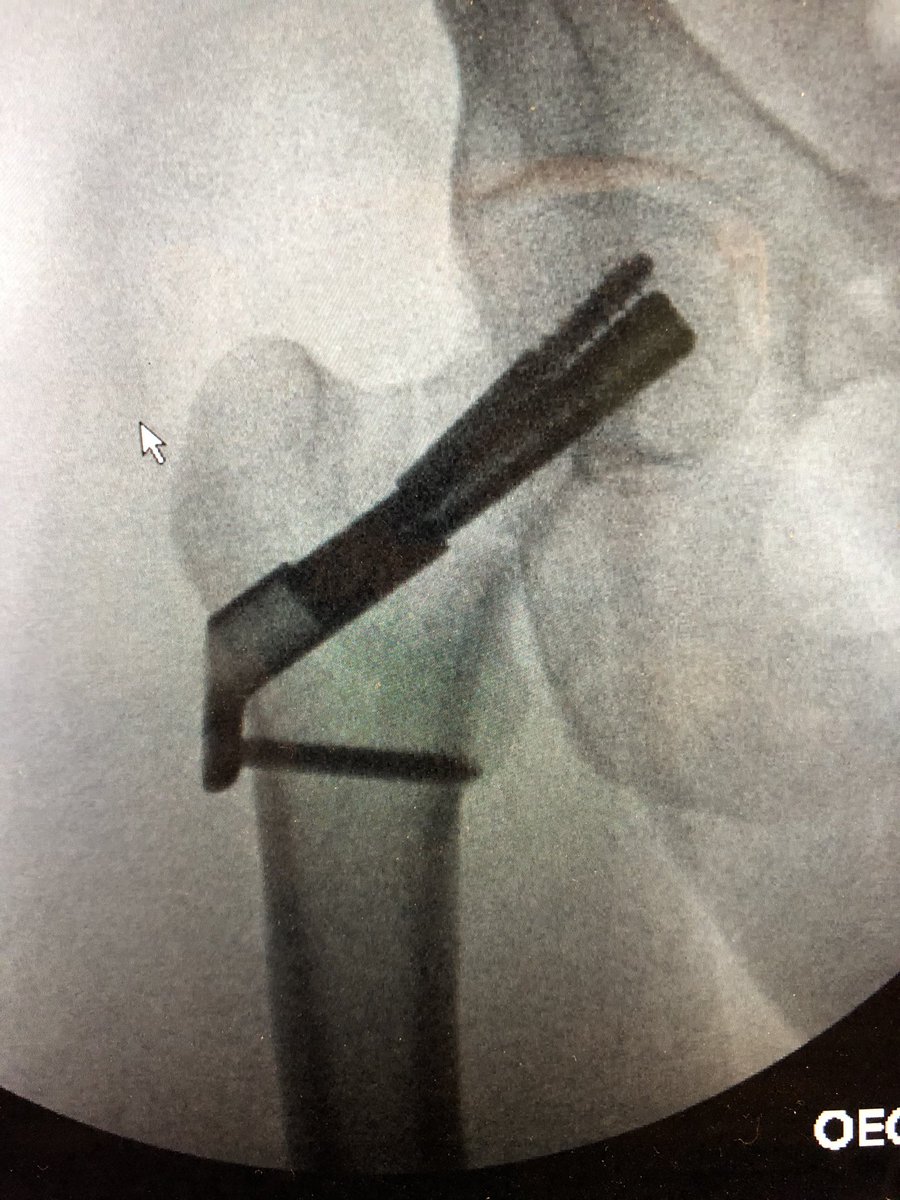

Just a little midnight fun when not on call #orthotrauma #HopkinsOrtho #femoralneckfracture #openreduction #SmithPetersen #lifeinthetimeofcovid19 #fns

@starsmore_j It is DePuy Synthes “FNS-Femoral Neck System”